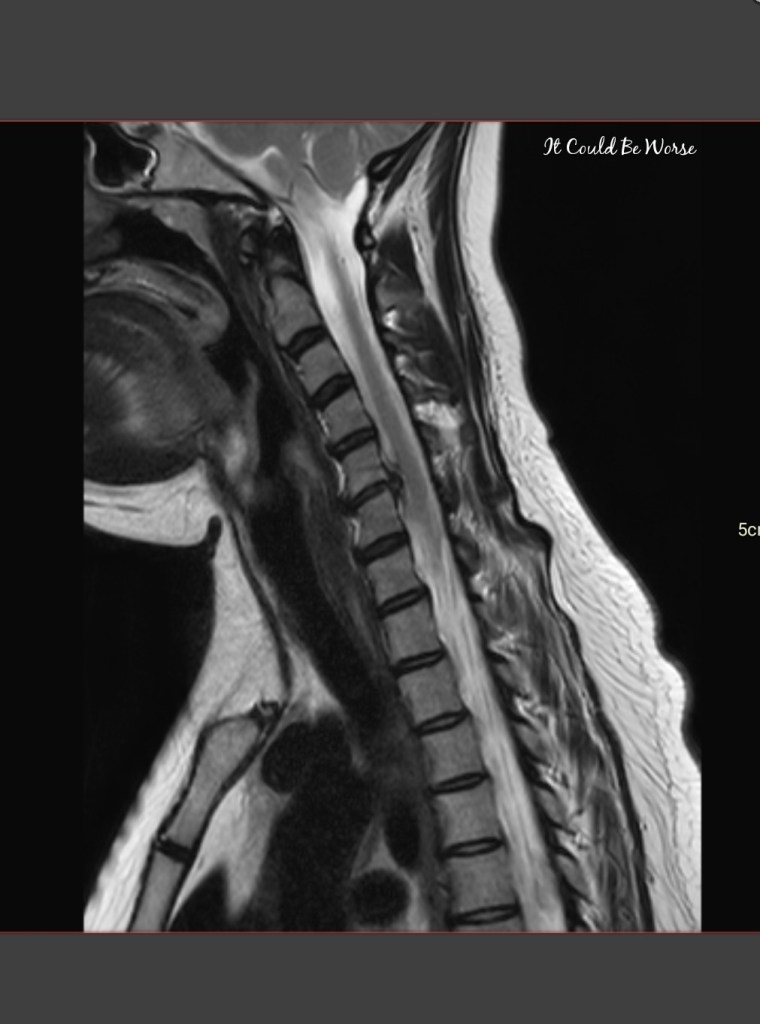

If you look at previous posts, my neck and herniated disc have been causing me some pain, tightness, and, numbness down both of my arms and hands.

What started out as random neck pain that would come and go after a few days, with sharp pains and being unable to move my neck much, has now turned into almost constant nerve and neck pain, hand, and finger numbness, with lightheadedness, and dizzy spells.

I was seeing a chiropractor last year for my neck – almost 20 days in a row – and each morning, my neck needed adjustments again and again and again. My chiropractor had told me I suffer from a herniated disc on my spinal cord and whip-lash. He also said that my neck has been suffering for so long, that it was going to take surgery to correct.

So, after I saw my neurosurgery team again, we planned for surgery in 2 weeks for an anterior cervical discectomy and fusion (ACDF) for my C5-C6 section of my neck, the most herniated area.